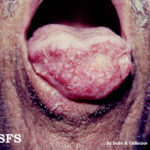

- Skin lesions are the most common manifestation of extrapulmonary disease. Cutaneous lesions favor exposed areas and enlarge over many weeks, from pimples that are minimally tender to well-circumscribed verrucous or ulcerative lesions, often with little inflammation. Verrucous lesions demonstrate raised irregular borders with crusting and purulent drainage, whereas ulcerative lesions are characterized by sharp and heaped-up borders with centrally located granulation tissue and exudate.

- Other unusual metastatic sites of infection include larynx, reticuloendothelial system (liver, spleen, lymph nodes, bone marrow), oropharynx, nose, and thyroid.